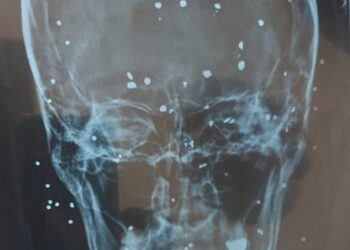

Iranian security forces are targeting women at anti-regime protests with shotgun fire to their faces, breasts and genitals, according to...